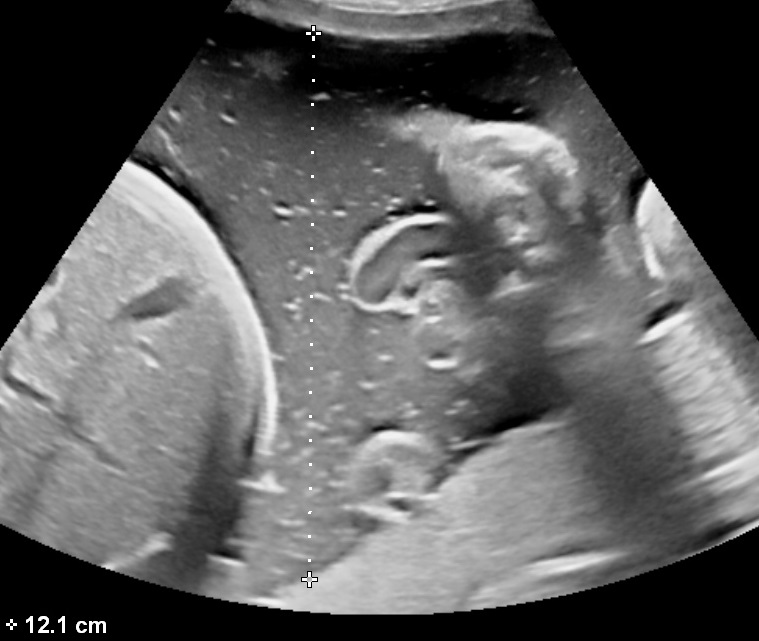

- Single Deepest Pocket (SDP)

The measurement is performed with the ultrasound probe at a right angle with the uterine wall. Measurements should exclude the umbilical cord or fetal parts. The width of each measured pocket must be at least 1 cm. Normal values range between 2-8 cm. It is also the preferred method for estimating the amniotic fluid volume in twin pregnancies.

Both semi-quantitative measurement techniques correlate poorly with the actual amniotic fluid volume.